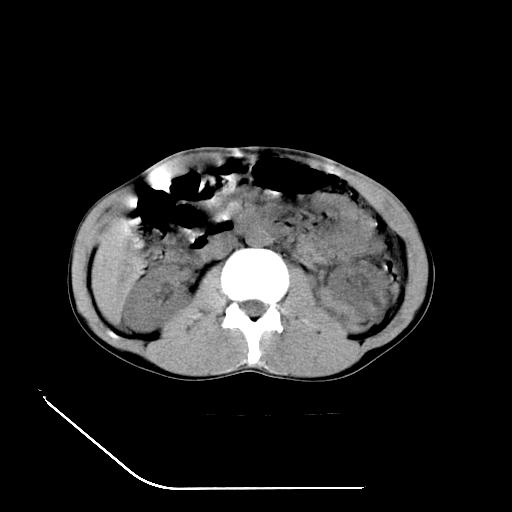

m-25y 高空堕落 12 月5号

12月7号病人尿量200ml/24h 急查双肾ct

左肾挫裂伤并肾周血肿;

肝肾间隙可见液区,建议手术探查;

左肾挫裂伤并肾周血肿

支持 : 左肾挫裂伤并肾周血肿

支持:1、左肾挫裂伤并肾周血肿;

2、少量腹水;

3、左肾旋转不良;

4、反射性肠淤张。

除了1:左肾挫裂伤并肾周血肿;

2:少量腹水

第二次ct检查后:临床医生腹水穿刺后考虑肠系膜动脉破裂,后实行剖腹探查:于空肠距离十二指肠90cm处发现肠管破裂,破裂口较小;修补后关腹。